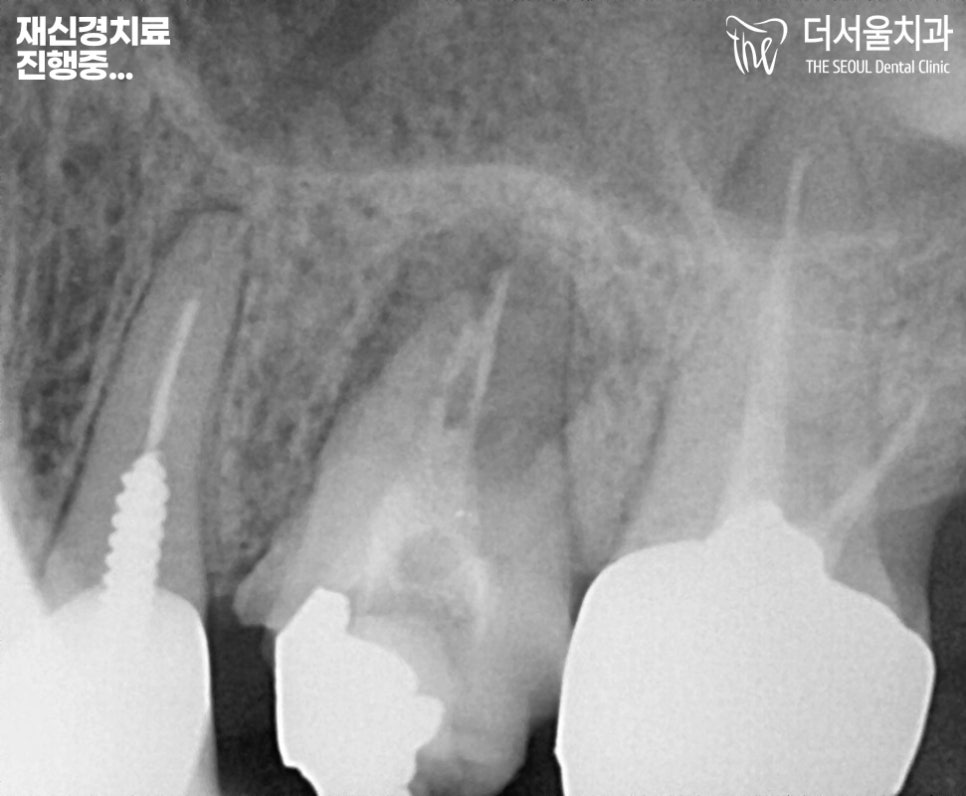

『재신경치료 진행중…

야탑역치과 잘하는곳』

문제 있는 26번 어금니의 크라운을 제거 후,

재신경치료에 들어갔습니다.

이후 충전 재료로 다시 채워놓은 뒤에

크라운을 수복해 드렸는데요.

재신경치료로 여러번 근관을 소독하고

감염된 것을 제거하고

반복되는 과정을 거친 뒤,

크라운을 수복하기 전에

충전 재료로 빈 곳을 채워줍니다.

그 후 모양을 다듬어

크라운이 잘 씌워질 수 있게끔

형태를 다듬어줍니다.